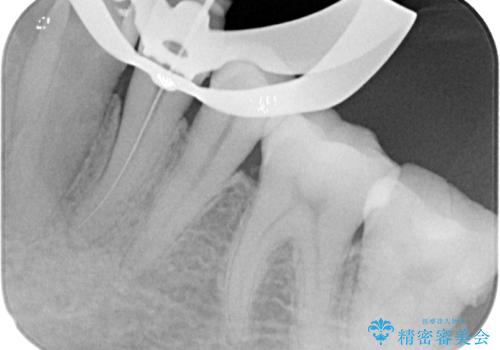

精査の結果、左下の第一小臼歯の虫歯が大きく進行していることが原因で痛みが出ていることがわかりました。

ラバーダム防湿を行ったうえで根管治療を行い、その後オールセラミッククラウンによる補綴治療を行っていくこととしました。

根管治療後すぐに痛みは消失しました。

根管治療後はクラウンによる補綴治療が必要です。